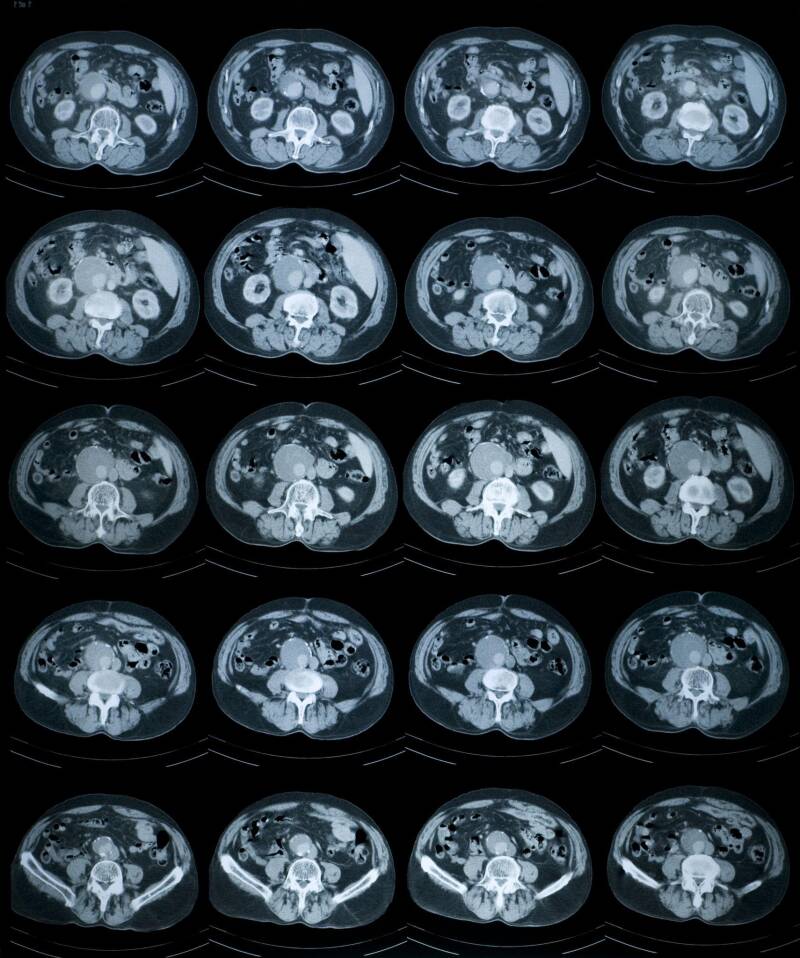

CT Scan (Computed Tomography)

A CT scan also uses X-rays — but in a much more advanced way.

Instead of a single flat image, it creates:

Layered cross-sections

- Detailed 3D-style images

- CT scans are particularly useful for: Complex fractures, Internal bleeding, Head injuries, Chest and abdominal problems.

Think of CT as a more detailed, multi-layered version of an X-ray.

It’s still mainly focused on structure, especially bone and internal organs — but it’s not the best tool for subtle soft-tissue problems in the spine.